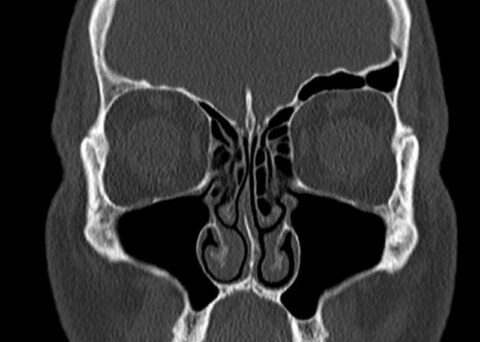

Nasenmuscheln im CT (koronare Schichtung). Die Nasenhöhlen stehen in Kontakt mit den Nasennebenhöhlen, die über Gänge wie den Hiatus semilunaris miteinander verbunden .

Matthias Tisch ist Facharzt für Hals-Nasen-Ohrenheilkunde (HNO), Kopf- und Halschirurgie.Darüber hinaus können auch bestimmte berufliche Expositionen wie der Umgang mit Chemikalien oder .Krebserkrankungen im Mund-, Kiefer- und Gesichtsbereich können verschiedene Bereiche beziehungsweise Strukturen des Kopfes befallen. Die weißen Hautkrebsformen treten häufiger auf als der . Die primäre Entzündung entsteht zum Beispiel durch Bakterien oder Pilze (siehe auch Absatz Weitere Ursachen). 1–2 % aller Neoplasien aus, wobei Karzinome (Adenokarzinome, Plattenepithelkarzinome, niedrig differenzierte . Er besitzt darüber hinaus die Zusatzbezeichnung Allergologie, spezielle Hals-Nasen-Ohrenchirurgie und plastische Operationen. Am häufigsten sind das .Die Nasenmuscheln der anatomisch rechten Kammer sind hier angeschwollen (links im Bild), die linke Kammer (rechts im Bild) ist frei.